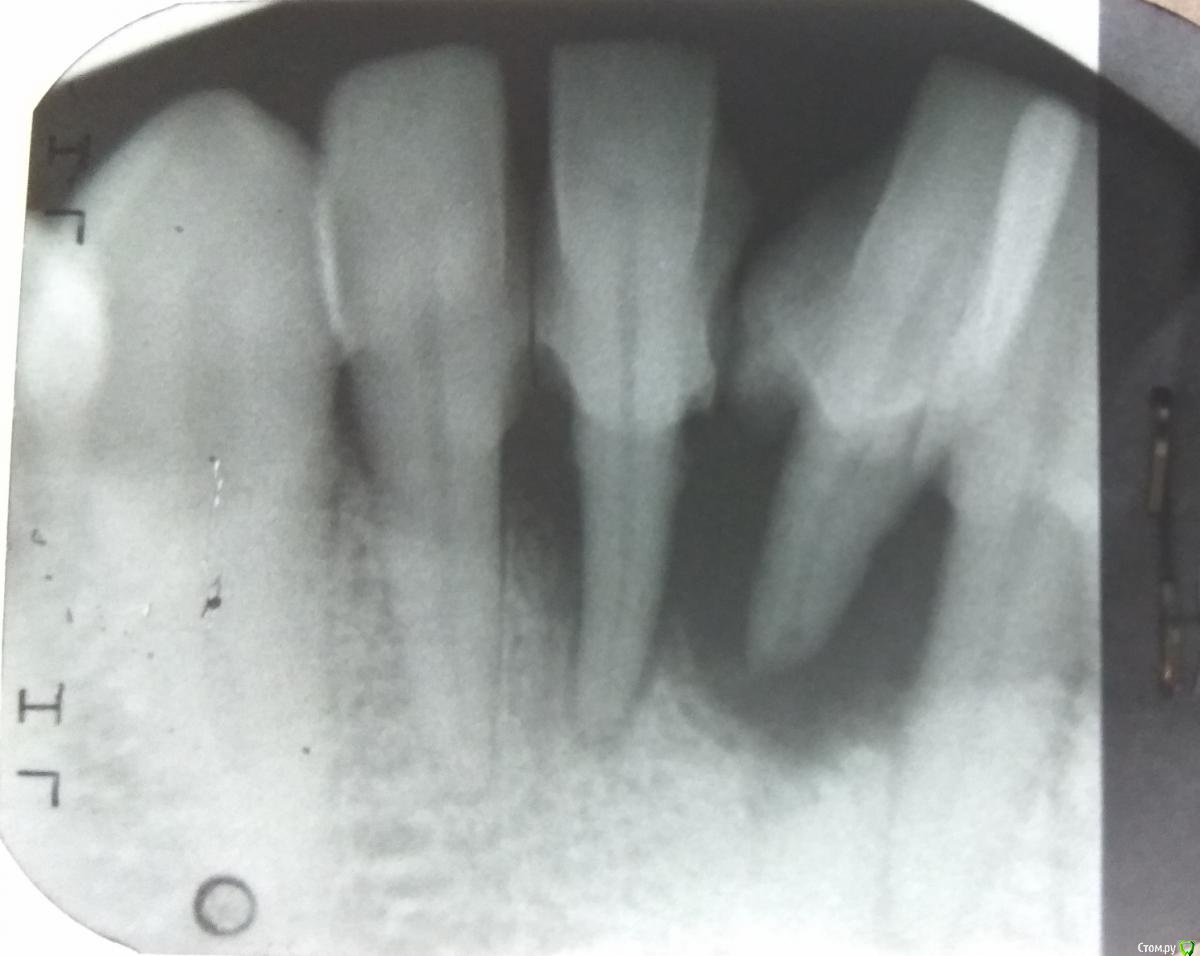

maskaads Опубликовано 13 мая, 2018 Поделиться Опубликовано 13 мая, 2018 Добрый день уважаемые специалисты. Моя проблема это поражение десны пародонтом до такой степени, что центральный нижний зуб стал сильно подвижным. Стоматолог провел санацию и закрытый кюретаж на 41,42,31,32, рекомендовал однозначно удалять зуб с последующей имплантацией и подсыпкой кости. Открытый кюретаж не делал сказал что зуб останется на десне. Возможно ли спасти зуб с помощью фотодинамической терапии для удаления новообразований и последующей подсыпкой кости. Или же это процедура в моем случае напрасна и уже не даст результата. Какие посоветуете варианты лечения для моего случая, потому как большинство стоматологов к которым я обращался говорят что мой случай безнадежен. Надеюсь на Ваш богатый опыт и желание помочь пациенту. Большое спасибо. Ссылка на комментарий

Bier Опубликовано 13 мая, 2018 Поделиться Опубликовано 13 мая, 2018 у двух ваших зубов уже никаких шансов нет вообще. Ссылка на комментарий

Борис80 Опубликовано 15 мая, 2018 Поделиться Опубликовано 15 мая, 2018 вашего снимка недостаточно для предстваления всех возможных вариантов, но они точно есть и их несколько Ссылка на комментарий

Irouil Опубликовано 15 мая, 2018 Поделиться Опубликовано 15 мая, 2018 Если решитесь прощаться с двойками - импланируйтесь одномоментно и ставьте мост на имплантатах. С большой долей вероятности это возможно. В идеале вообще сразу временный мост на имплантатах с удалением всех 4 зубов. Но нужно смотреть КТ Ссылка на комментарий